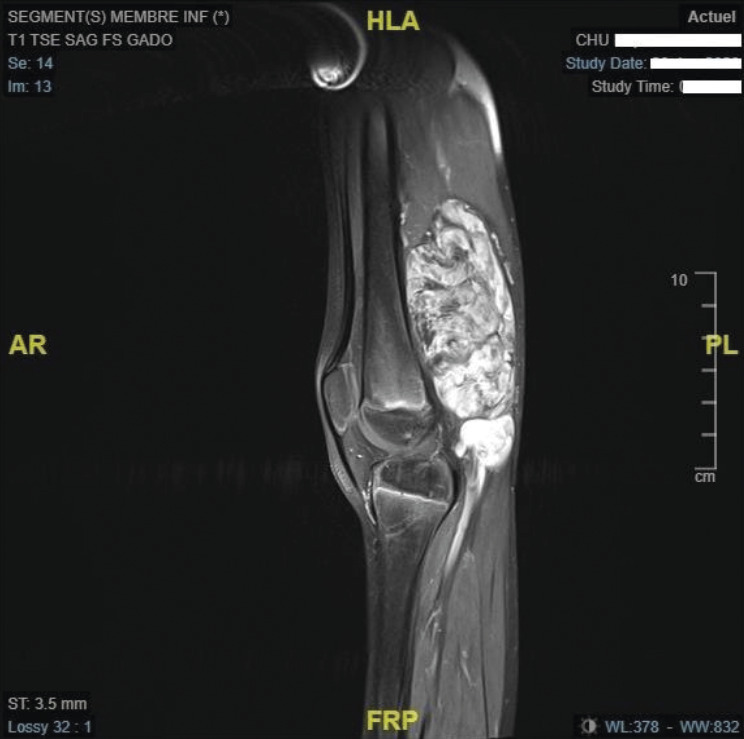

L’IRM confirme l’existence d’une masse tissulaire avec contingent graisseux refoulant les structures de voisinage (figures ).

L’IRM confirme l’existence d’une masse tissulaire avec contingent graisseux refoulant les structures de voisinage (